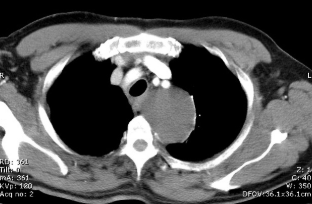

2 anos, masculino

Cisto de duplicação esofágico

Predleção por meninos; diagnosticados na infância

Em geral assintomáticos; podem provocar estridor

Mais comuns no esôfago distal; geralmente não comunicam com a luz do esôfago;

TC: Cisto com densidade de líquido, margens bem definidas que podem realçar com contraste; podem complicar com hemorragia, infecção: nível liquido, espessamento parietal.